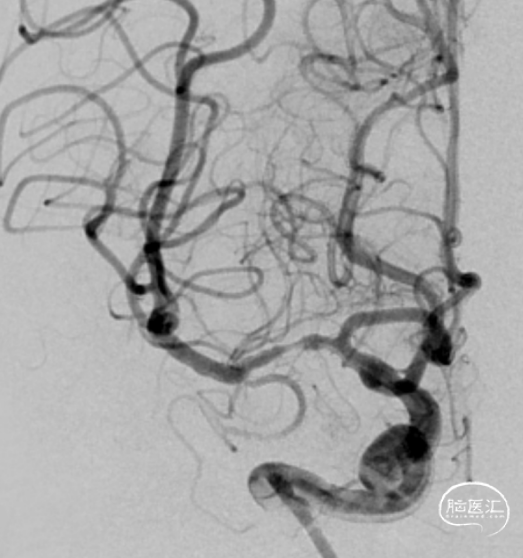

复查造影见支架展开良好,支架内及远端血流通畅,TICI分级3级。术顺,术毕,Proglide缝合术口。

术后第一天复查颅脑CT未见异常染色及大面低密度病灶。

查头颅MRI:右侧基底节区、右侧顶颞岛叶急性脑梗死。